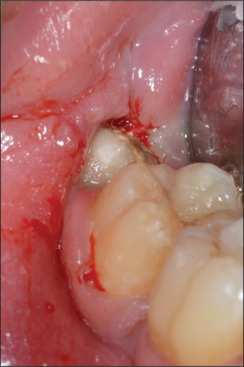

Materials and methods: This article describes the planning process and the extraction of a lower third molar with the inferior alveolar nerve (IAN) entrapped through its roots using the 3D reconstruction of a CBCT scan.

Results: After-surgery clinical examinations showed normal healing of the surgical wound and no neurological symptoms.